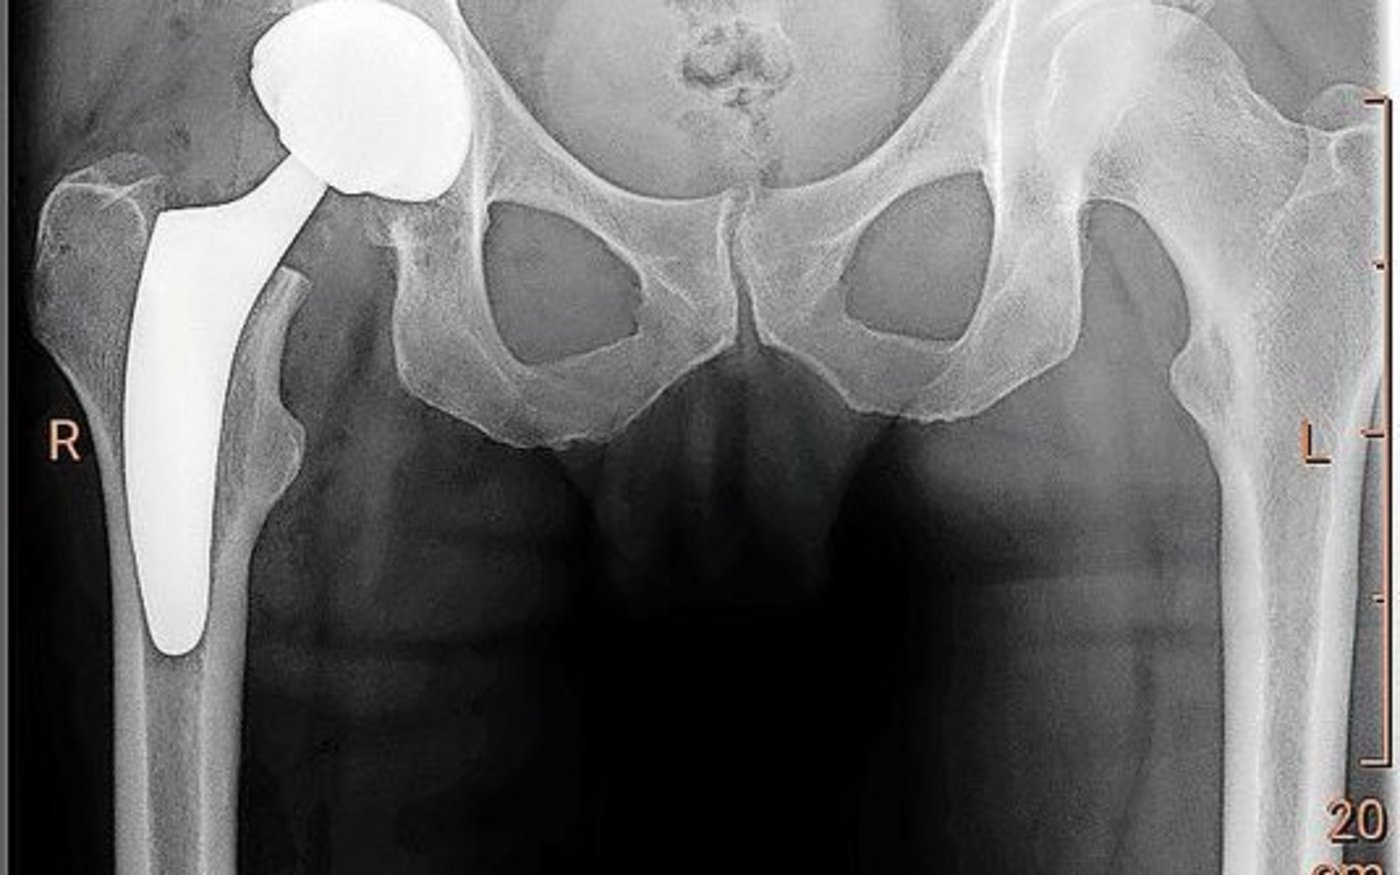

Körperliche Beschwerden sind in der Landwirtschaft weitverbreitet – oft wartet man zu lange

Hier hat unser Zentralschweizer Redaktionskollege Reto Betschart einen sehr ausführlichen Artikel zusammengestellt – das Ganze war ja auch ein doppelseitiges Thema der Woche. Dass er diesen Raum beansprucht hat, ist gut, denn sein Interview mit dem Spezialarzt Robert Seidner dreht sich um die bäuerliche Gesundheit und damit um ein wichtiges Thema. Beim Interview haben Reto und Dr. Seidner über Beschwerden und Prophylaxe gesprochen und darüber, wann es definitiv Zeit ist, zum Arzt zu gehen. Das ist meistens früher als man denkt – entsprechend wichtig finde ich den Artikel.